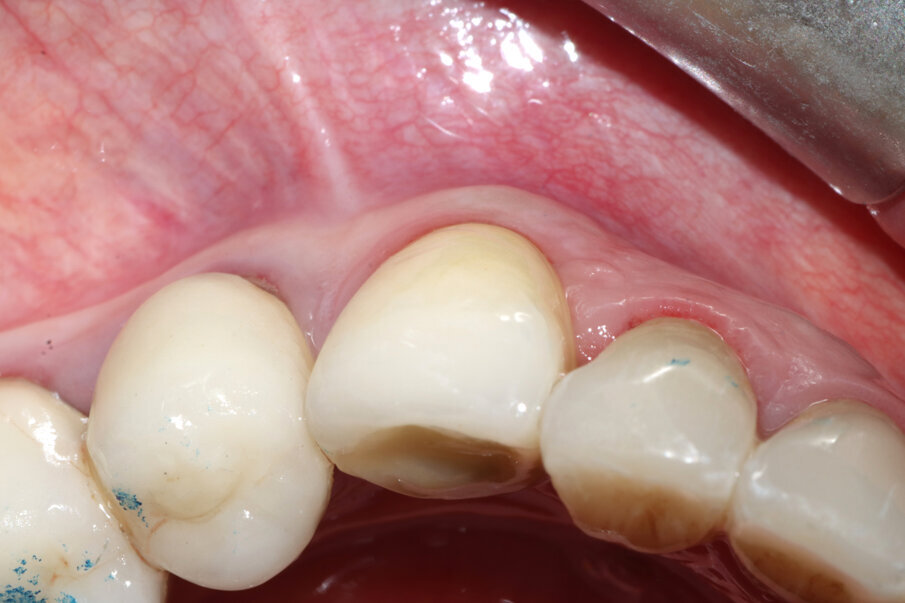

Il risultato finale è una corona protesica attorno alla quale risultano perfettamente mantenuti tutti i volumi: bozza canina vestibolare, margine gengivale e papille interdentali (Figg. 15-20).

Figg. 16, 17_Visione occlusale dei tessuti guariti e alla consegna della corona; si noti il mantenimento della bozza canina.

Figg. 18, 19_Visione laterale dei tessuti guariti e alla consegna della corona; si noti la presenza delle papille.